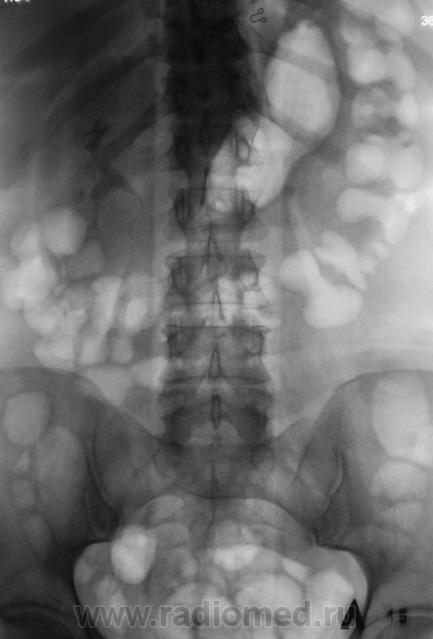

Пациент направлен на внутривенную урографию.

Камень в левом мочеточнике.

В верхней трети.

Мне кажется, неправомочно говорить о камне мочеточника слева, т.к. не видим контрастирования собирательной системы левой почки.Последний снимок выполнен на 15 минуте, конечно надо было выполнить снимки на 40 минуте , а может быть в дальнейшем и позже по времени.

Конечно есть. Да, и "блок" левой почки свидетельствует, да и УЗИ подтвердило.